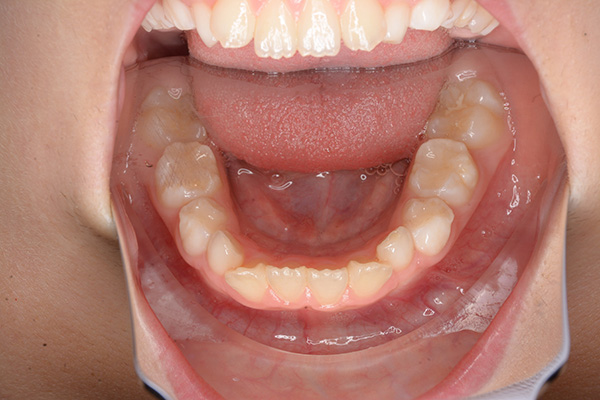

口腔内所見 over jet 7.5mm,over bite 3.5mm,大臼歯関係はⅡ級 。Hellmanのdental ageはⅢAであり上突咬合を呈していた。

批評・予后 本来であれば永久歯歯列完成後に本格矯正治療を行って良い症例だが、患者さん(保護者)の強い希望から早期治療にて改善を行った症例である。バイオネーターを夜間就寝中に使用して咬合誘導を行った結果、前歯の前突感は解消され比較的緊密な咬合は得られたように思う。

使用装置 バイオネーター